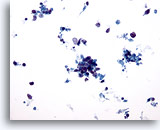

画像 3:肺FNA、肺大細胞癌 腫瘍細胞は、このシート内に見られる数個のアポトーシス細胞より大型です。細胞質の保存状態は良好であり、量が中程度で密度が高く、微細な空胞化が見られます。扁平上皮への分化の特徴である細胞間橋を思わせる細胞変化が局所的に見られます。核は円形から卵円形を呈し、結合性が疎のクロマチン集塊および肥厚化した滑面核膜が認められます。核小体は目立ち、不整形を呈し、単個から複数個見られます。高いN/C比を示します。

60倍

画像 3

肺FNA、肺大細胞癌

腫瘍細胞は、このシート内に見られる数個のアポトーシス細胞より大型です。細胞質の保存状態は良好であり、量が中程度で密度が高く、微細な空胞化が見られます。扁平上皮への分化の特徴である細胞間橋を思わせる細胞変化が局所的に見られます。核は円形から卵円形を呈し、結合性が疎のクロマチン集塊および肥厚化した滑面核膜が認められます。核小体は目立ち、不整形を呈し、単個から複数個見られます。高いN/C比を示します。

60倍